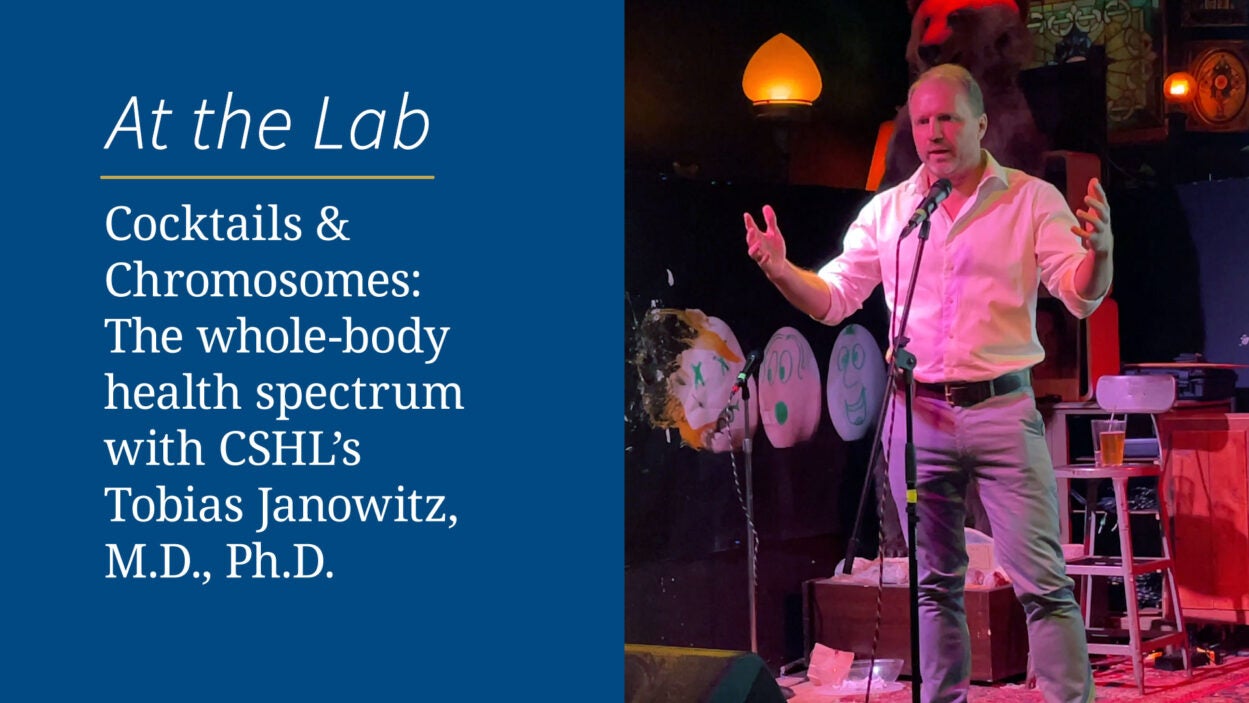

As a physician-scientist at CSHL, Tobias Janowitz has led early-phase clinical trials to develop therapeutic strategies for patients with cancer. Read the story »

The popular CSHL event series returns to Industry Lounge on January 30, 2025. In the meantime, check out some highlights from last year’s talks. Watch the video »

How can a tiny tumor, often no larger than a penny, have such a big impact? CSHL’s Tobias Janowitz unpacks a complicated but highly relatable issue. Watch the video »

CSHL Associate Professor Tobias Janowitz and colleagues discover the brain-body connection underlying apathy in the late stages of cancer. Read the story »